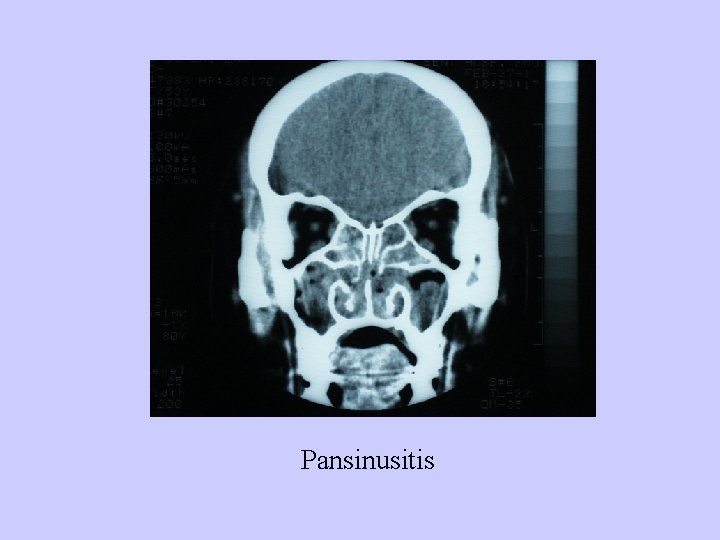

Pansinusitis

Pansinusitis